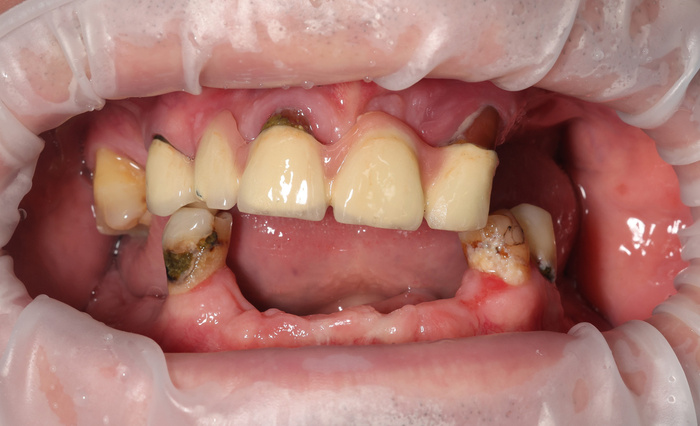

Осталось сдать финальную работу. Вот с этого момента у многих и начинаются проблемы - перекосы, сколы, ощущение чужеродной лопаты во рту.

При установке имплантатов "на глаз" до мм рассчитать углы наклона "болтов" крайне затруднительно, перекосы будут. Протез нужно адаптировать к положению имплантатов. Расчёты, проведённые ДО имплантации, дают преимущество - имплантаты в чётких позициях и под чёткими углами в кости. Не протез адаптируется к постановке имплантатов, а имплантаты к протезу - по шаблонам.

Могут быть с такой работой проблемы? Да, могут. Но это умудриться надо.

Посмотрим, что во рту:

Временный адаптационный протез с опорой на 6 имплантов. Нижняя челюсть.

До.

До имплантации.

А вот что стало после.